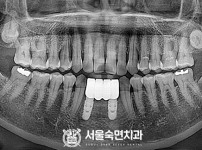

임플란트-전후사진4